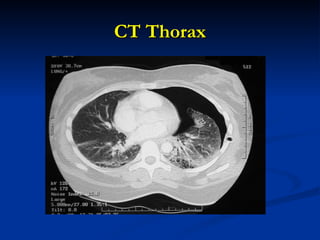

CT Thorax

• 29.